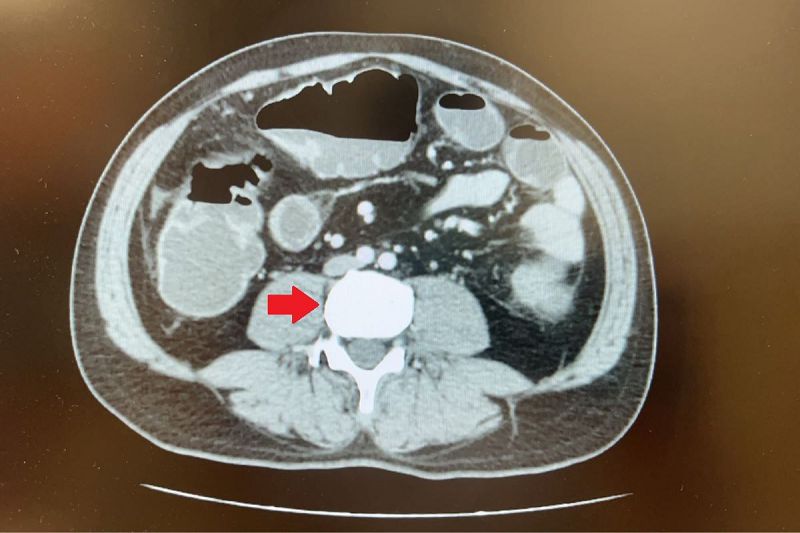

向來健康,沒有家族史的45歲蘇先生,日前長達三天都無排氣、排便,因而腹脹無法進食,至台北慈濟醫院急診就醫。電腦斷層檢查發現他降結腸處有一顆5公分的大腫瘤,導致腸道完全阻塞。醫療團隊高度懷疑大腸癌,但由於腸阻塞無法施行大腸鏡檢查,在與病人討論後,大腸直腸外科陳昱廷醫師為他安排手術切除腫瘤、周圍腸段及淋巴節,術後病理報告確定為已有淋巴轉移的大腸癌第三期,進一步安排後續化學治療。

臨床上,大腸癌以大腸鏡檢查搭配病理切片判定為主,但會搭配電腦斷層、核磁共振甚至是正子攝影等影像檢查,確認是否有侵犯、阻塞或轉移,進而決定手術方式。陳昱廷醫師說明,目前大腸癌手術已非常成熟,常見方式包含開腹手術、腹腔鏡微創手術、單孔微創手術與達文西機器手臂輔助手術等。其中微創手術傷口小、恢復快,但對於腸道嚴重阻塞或腹腔沾黏嚴重的個案,仍以開腹方式較為安全,除了切除腫瘤外,也會同步切除前後腸段作為安全距離,並清除病灶周圍的淋巴,以根除癌細胞。術後則會視病人癌別與以化學治療、放射線治療等輔助治療;但若已經是第四期的病人,會以其他治療為主,手術為其二線選擇。整體來看,隨著醫療進步,即使是第三期大腸癌,手術切除後的五年存活率有五至六成,早期發現更可達九成以上。